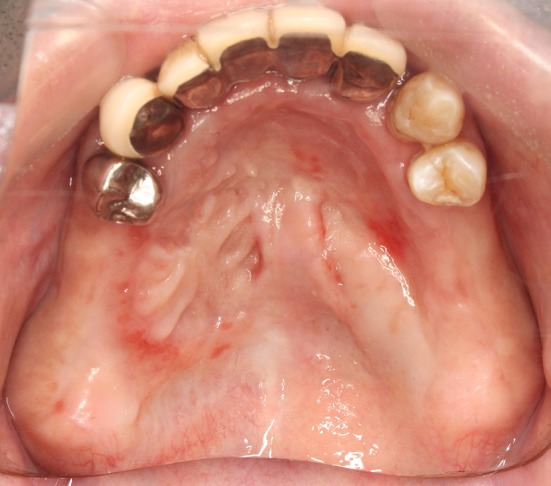

Fig. 10.

Two months after the closure operation. The mucoperiosteal flap was completely engrafted. We confirmed the complete epithelization of the donor part

The mucoperiosteal flap was completely engrafted. There were no ruptured sutures or wound infection. Two months later, we confirmed the complete epithelization of the artificial dermis in the area (Fig. 10). The manifestation of maxillary sinusitis also improved.